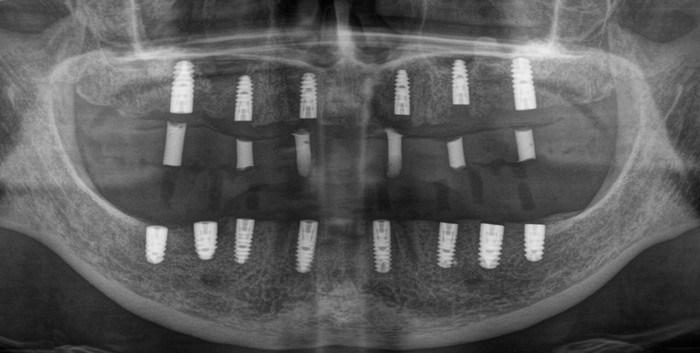

Ниже панорамный снимок зубов пациентки

Вот на кой хер при такой ширине альвеолярной части установили средневековый пластиночный имплантат, остается для меня загадкой.

Итак, после того как были учтены результаты диагностики, консультация ортопеда и (что немаловажно) пожелания пациента (!), было принято решение об удалении всех зубов на верхней и нижней челюсти, в том числе установленных ранее имплантатов. Кроме пластиночного. Его я оставил на десерт.

На верхней челюсти были установлены шесть имплантатов и проведена операция по наращиванию костной ткани – синус-лифтинг (с обеих сторон). Через 2 недели установлены 8 имплантатов на нижней челюсти.

Панорамный снимок зубов